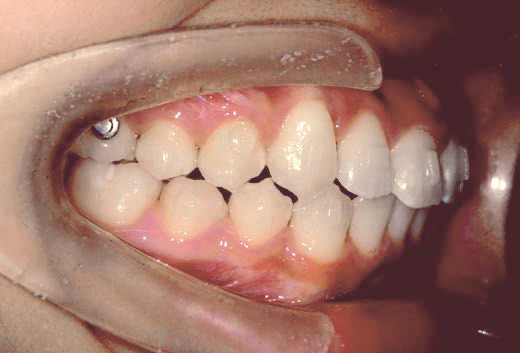

下の奥歯が内側に傾いて、舌の位置が悪く、鼻がつまって口呼吸の状態でした。扁桃腺がよく腫れ、風邪をひきやすく、いびきもあるようでした。

治療を終えて

装置で上あごを拡大し、下の歯の位置を整え、前歯の並びを整えました。お口のトレーニングの効果で鼻詰まりと、いびきも改善。たった1年でこの変化が見られました。もちろん歯は1本も抜いていません。

主訴・治療内容 他院にて「抜歯した上で、ワイヤーを付け、5年かけて治療する」と言われ、他の方法はないのかとネットで調べたところ、当院を知り無料相談に来院されました。